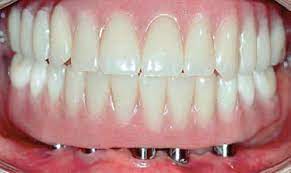

(42.) Fixed-removable prosthesis.

Figure 42

(43.) Fixed-removable prosthesis.

Figure 43

(44.) Fixed-removable prosthesis.

Figure 44

(45.) Fixed-removable prosthesis.

Figure 45

At the initial patient examination, several factors in addition to restoration shape should be considered when planning implant-supported restorations. History of periodontal disease, irregular maintenance visits, clinical appearance of the remaining teeth and soft tissue conditions may indicate increased risk of peri-implantitis. Patient dexterity, adaptability, willingness, and capability to carry out intended home care should be considered. Patient's mental conditions including dementia may influence the design of this as well as unrealistic patient expectations. A "High water original Branemark design" or no treatment may be indicated. Especially when implant location makes access, a fixed-removable design may be necessary to reduce risk of peri-implantitis may be indicated (Figures 42 through Figure 45). Considering that oral biofilm accumulation, even at two weeks post prosthetic insertion is documented, periodic removal of screw retained restorations is less effective than daily access to disrupt bacterial plaque accumulation.